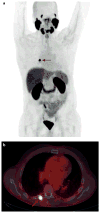

The oligometastatic state has been proposed as an intermediate stage of cancer spread between localized disease and widespread metastases. With improvements in diagnostic modalities such as functional imaging, oligometastatic prostate cancer is being diagnosed with greater frequency than ever before. Furthermore, the paradigm for treatment of advanced prostate cancers is shifting toward a more aggressive approach. Many questions surround the understanding of the process and consequences of oligometastasis, meaning that the contemporary literature offers a wide variety of definitions of oligometastatic prostate cancer. Until genomic data exist to provide a biological component to the definition of oligometastatic disease, a clinical diagnosis made on the basis of up to five extrapelvic lesions is reasonable for use. Retrospective studies suggest that interventions such as radical prostatectomy and local or metastasis-directed radiotherapy can be performed in the metastatic setting with minimal risk of toxic effects. These therapies seem to decrease the need for subsequent palliative interventions, but insufficient data are available to draw reliable conclusions regarding their effect on survival. Thus, a protocol for clinicians to manage the patient presenting with oligometastatic prostate cancer would be a useful clinical tool.